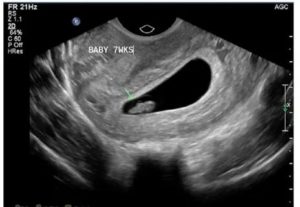

После 7-й недели для аборта обычно требуется расширение шеечного канала (используют аспирационную кюретку большего диаметра, поскольку плод увеличивается).

Как показывает практика, в 85% случаев замирание развития плода происходит до 10 недели вынашивания. Вплоть до 6 недели оплодотворённая клетка (зигота) находится в плодном яйце, которое уже прикрепилось к стенке плаценты в матке. Если происходит замирание на ранних сроках, то речь идет, скорее всего, об анэмбрионии первого или второго типа.

При первом типе зародыш не визуализируется, плодное яйцо не более 2,5 см, а размер тела матки соответствует 6 неделе беременности. При этом типе останавливается развитие и плода, и плодного яйца.

При втором типе анэмбрионии плодное яйцо развивается, в то время как ребенок уже нет. Остатки эмбриона не визуализируются, а размер плодного яйца соответствует 12 неделе беременности (примерно 4,5 см).